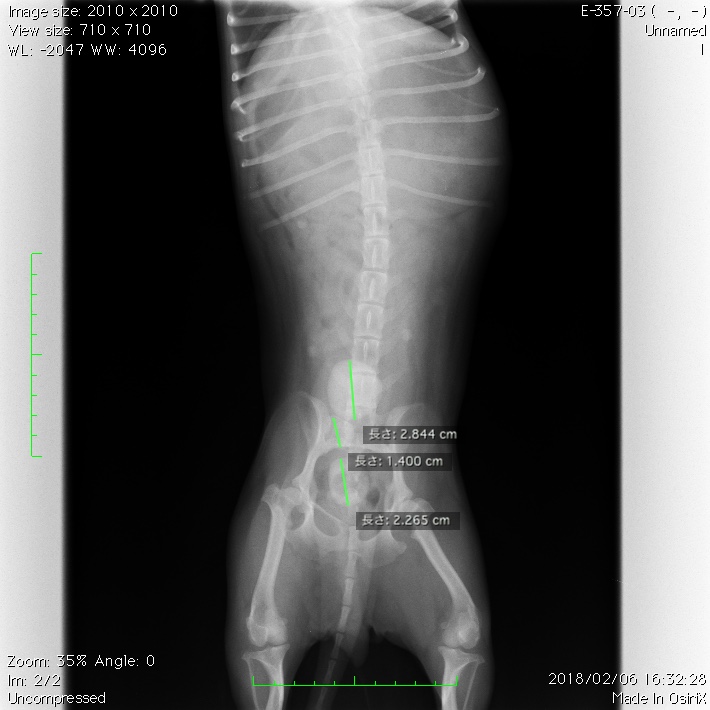

レントゲン検査では膀胱内に、3つのX線不透過性の物体が確認されました。(写真1、2)

写真1